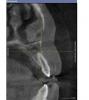

xo4ysoxranitzyb Опубликовано 17 августа, 2009 Поделиться Опубликовано 17 августа, 2009 Зравствуйте. Мне 22 года, девушка, г.Санкт-Петербург, гр.крови "1+".Мне лет 8 назад ставили пломбу(без удаления нерва) на 22 зуб(верхняя левая двоечка). 7 месяцев назад он стал побаливать - обратилась к стоматологу. Оказалось, что нерв умер сам по себе(не болезненно), а на зубе образовалась киста. Почистили каналы, поставили лекарство и временную пломбу - попробовали терапевтическое лечение. Но через две недели появилась припухлость десны в области корня 2-ки. Открыли зуб, разрезали десну с наружной стороны. В тот же день появилась припухлость десны с внутренней стороны. Антибиотики внутренне, антисептик(полоскание) - припухлость прошла. Болезненных ощущений не было. Зуб оставался открыт 6 месяцев(моя вина, надеялась - что пополощу травками - пройдет), во время еды вставляла ватку.Сейчас зуб начал побаливать. Обратилась к стоматологу. Начала терапевтическое лечение, пока - меняют лекарство через пару-тройку дней, пропила Ровамицин 7 дней. Не болит, не воспаляется. ------------Врач-терапевт говорит, что есть шанс вылечить терапевтически.Врач-хирург говорит, что киста очень большая, объемная и сложной формы. Что она очень близко расположена к носовой перегородке и к соседнему зубу. Что резекцию делать бесполезно, т.к. киста очень высоко поднялась по корню зуба. Что необходимо удалять зуб, причем срочно - т.к. она растет и скоро повредит носовую перегородку, а потом и соседний зуб(если еще не добралась до него).=====Подскажите, пожалуйста 1. Каков шанс вылечить терапевтически2. Возможна ли резекция верхушки корня, с сохранением зуба(!)3. Если нет возможности оставить зуб - то что будет вместо него(если вырезать кисту - то там практически нет надкостницы - не на что ставить имплант наверное). Но пилить соседние зубы - передние - это совсем плохо, я молодая еще.4. Куда лучше обратиться(поликлиника)ПОМОГИТЕ!!! Мне очень важно сохранить этот зуб! У меня на руках томограмма зубной полости, может какие другие снимки(ракурсы) прикрепить? Ссылка на комментарий